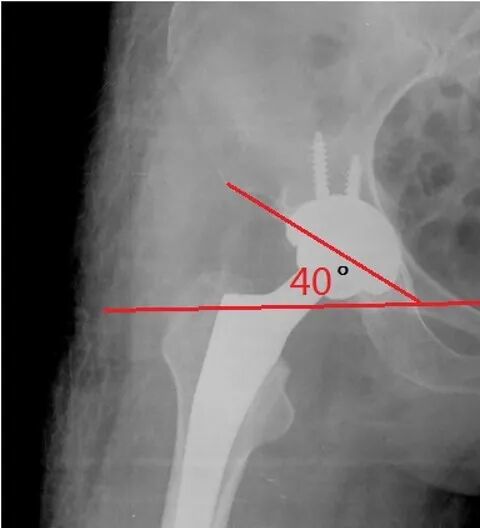

髋臼重建基本原则髋臼位置-优化-活动度/稳定性-45~55度外展

-15~20度前倾-根据解剖

髋臼俯倾

联合前倾角